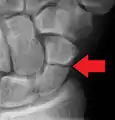

Radiolucency around a 12 days old scaphoid fracture that was initially barely visible.[10]